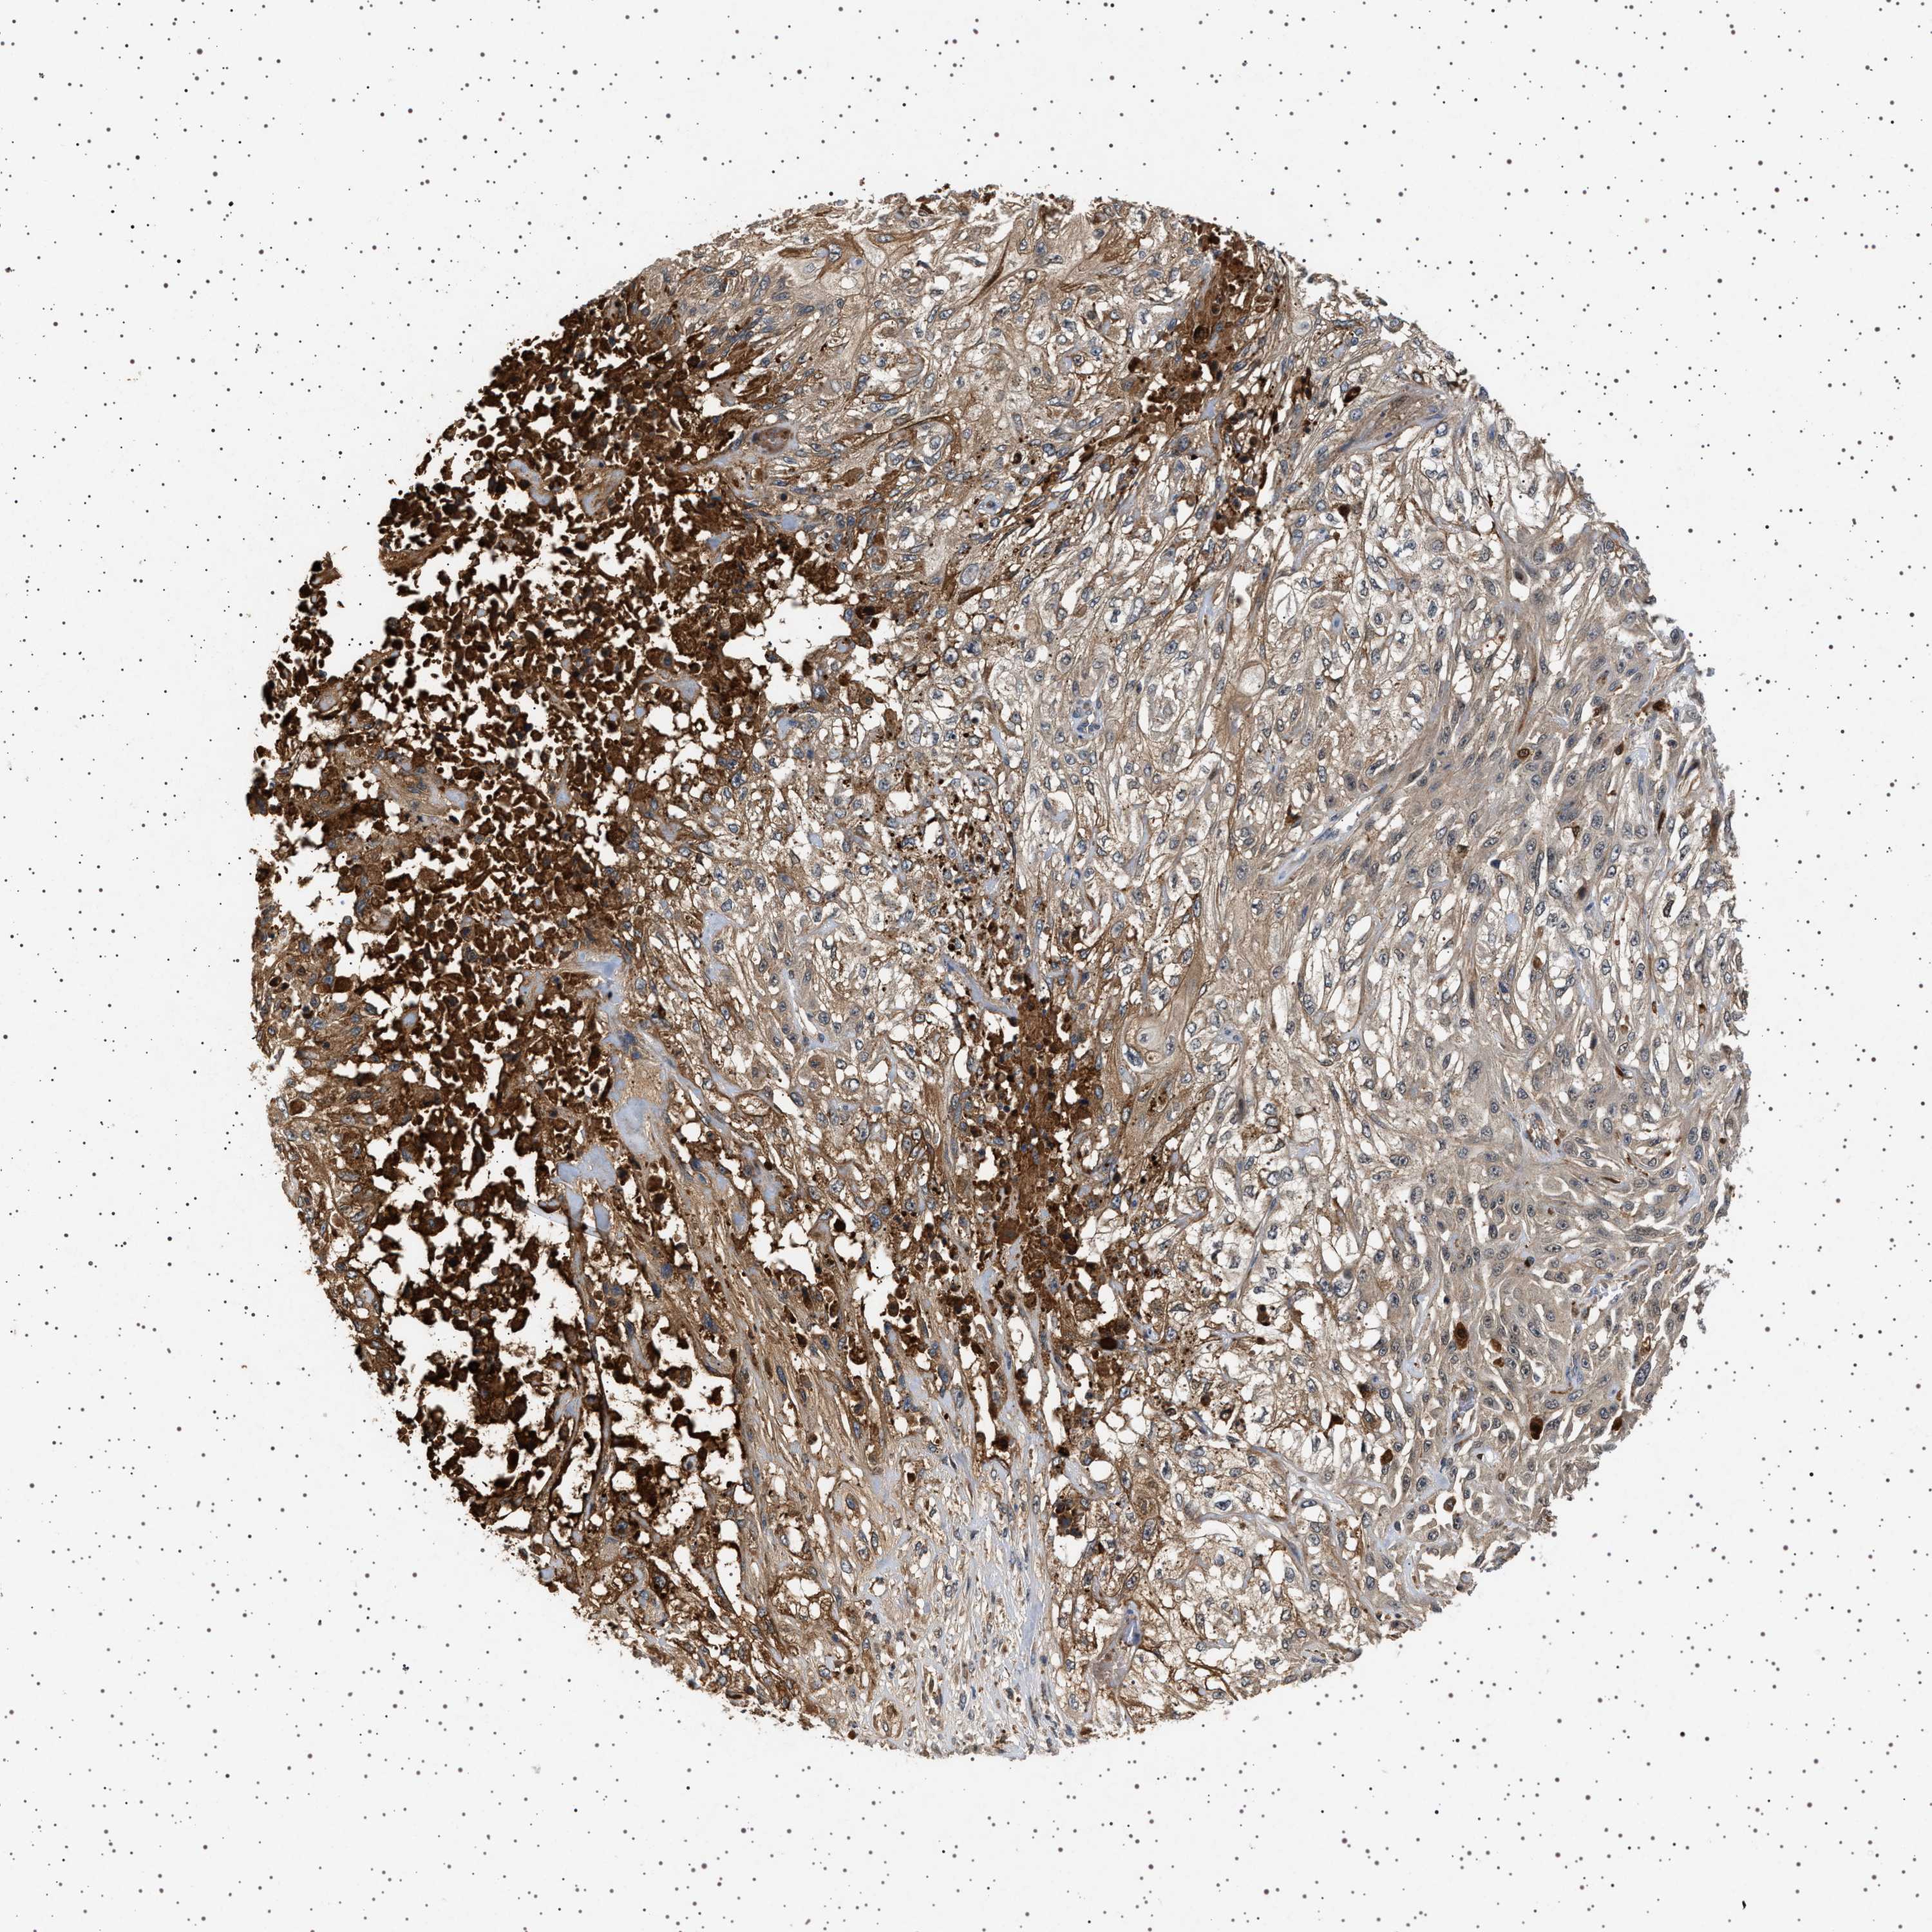

Basal cell and squamous cell cancer

SKIN CANCER - Protein expressioni

A mouse-over function shows sample information and annotation data. Click on an image to view it in a full screen mode. Samples can be filtered based on level of antibody staining by selecting one or several of the following categories: high, medium, low and not detected. The assay and annotation is described here.

Each image is clickable and will lead to virtual microscopy that enables deeper exploration of all samples and also displays staining intensity scores, fraction scores and subcellular localization as well as patient and tissue information for each sample.

Antibody HPA021390

Staining

High

Medium

Low

Not detected

Intensity

Strong

Moderate

Weak

Negative

Quantity

>75%

75%-25%

<25%

None

Location

Nuclear

Cytoplasmic/membranous

Cytoplasmic/membranous,nuclear

Basal cell carcinoma